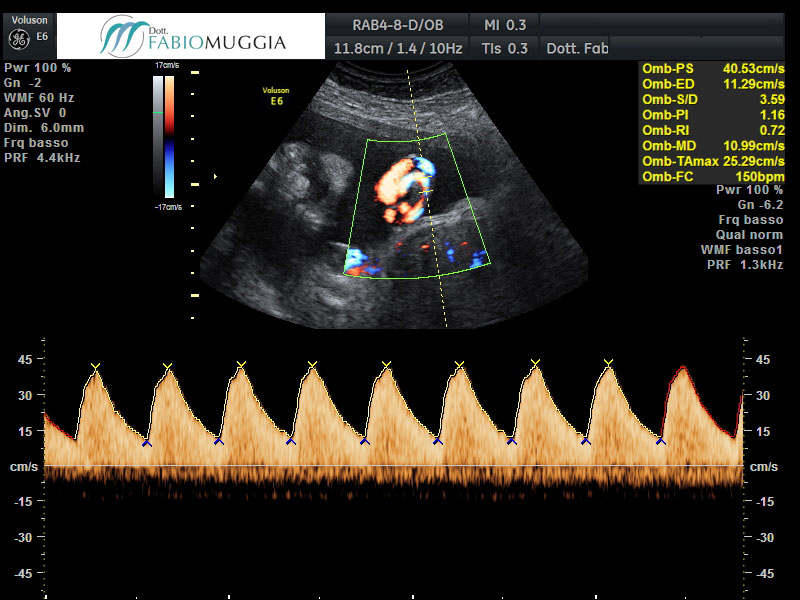

Sono disponibili numerose regolazioni automatiche a seconda del distretto corporeo fetale o della funzione circolatoria che vogliamo esaminare. Abbiamo infatti la possibilità di valutare non solo la conformazione di alcune strutture ed organi fetali, ma anche la possibilità di analizzare i flussi di sangue diretti dalla madre verso il feto, come anche le caratteristiche circolatorie all'interno del corpo fetale tramite l'esplorazione di diversi vasi arteriosi del feto mediante la tecnica ecografica Color-Doppler od HD-Flow.

L'ecografia è una tecnica di analisi davvero sempre più importante perché, con l'integrazione offerta dalle tecnica Doppler per l'analisi dei flussi sanguigni, che consente di capire se il “bambino” si sta sviluppando in condizioni di benessere, con scambi di ossigeno ottimali, oppure se il feto si sta sviluppando in un ambiente sfavorevole con scambi critici, ai livelli minimi di necessari, di ossigeno e di altre sostanze nutritive che gli provengono dalla madre. L'analisi ecografica tradizionale e l'importantissima integrazione apportata dalla Doppler-flussimetria, specie le più moderne recenti versioni tecnologiche, consentono al giorno d'oggi sia di gestire con notevole sicurezza la gravidanza dei “bambini” che dimostrano che di crescere poco, cioè affetti da "ritardo di crescita intra-uterino", sia addirittura di uscire a comprendere, allora anche largo anticipo, quelle che sono le donne che svilupperanno una gravidanza caratterizzata da "ritardo di crescita" (I. U. G. R. – Intra Uterine Growt Retardation) o "restrizione di crescita intrauterina” (F. G. R. – Fetal Growt Restriction).